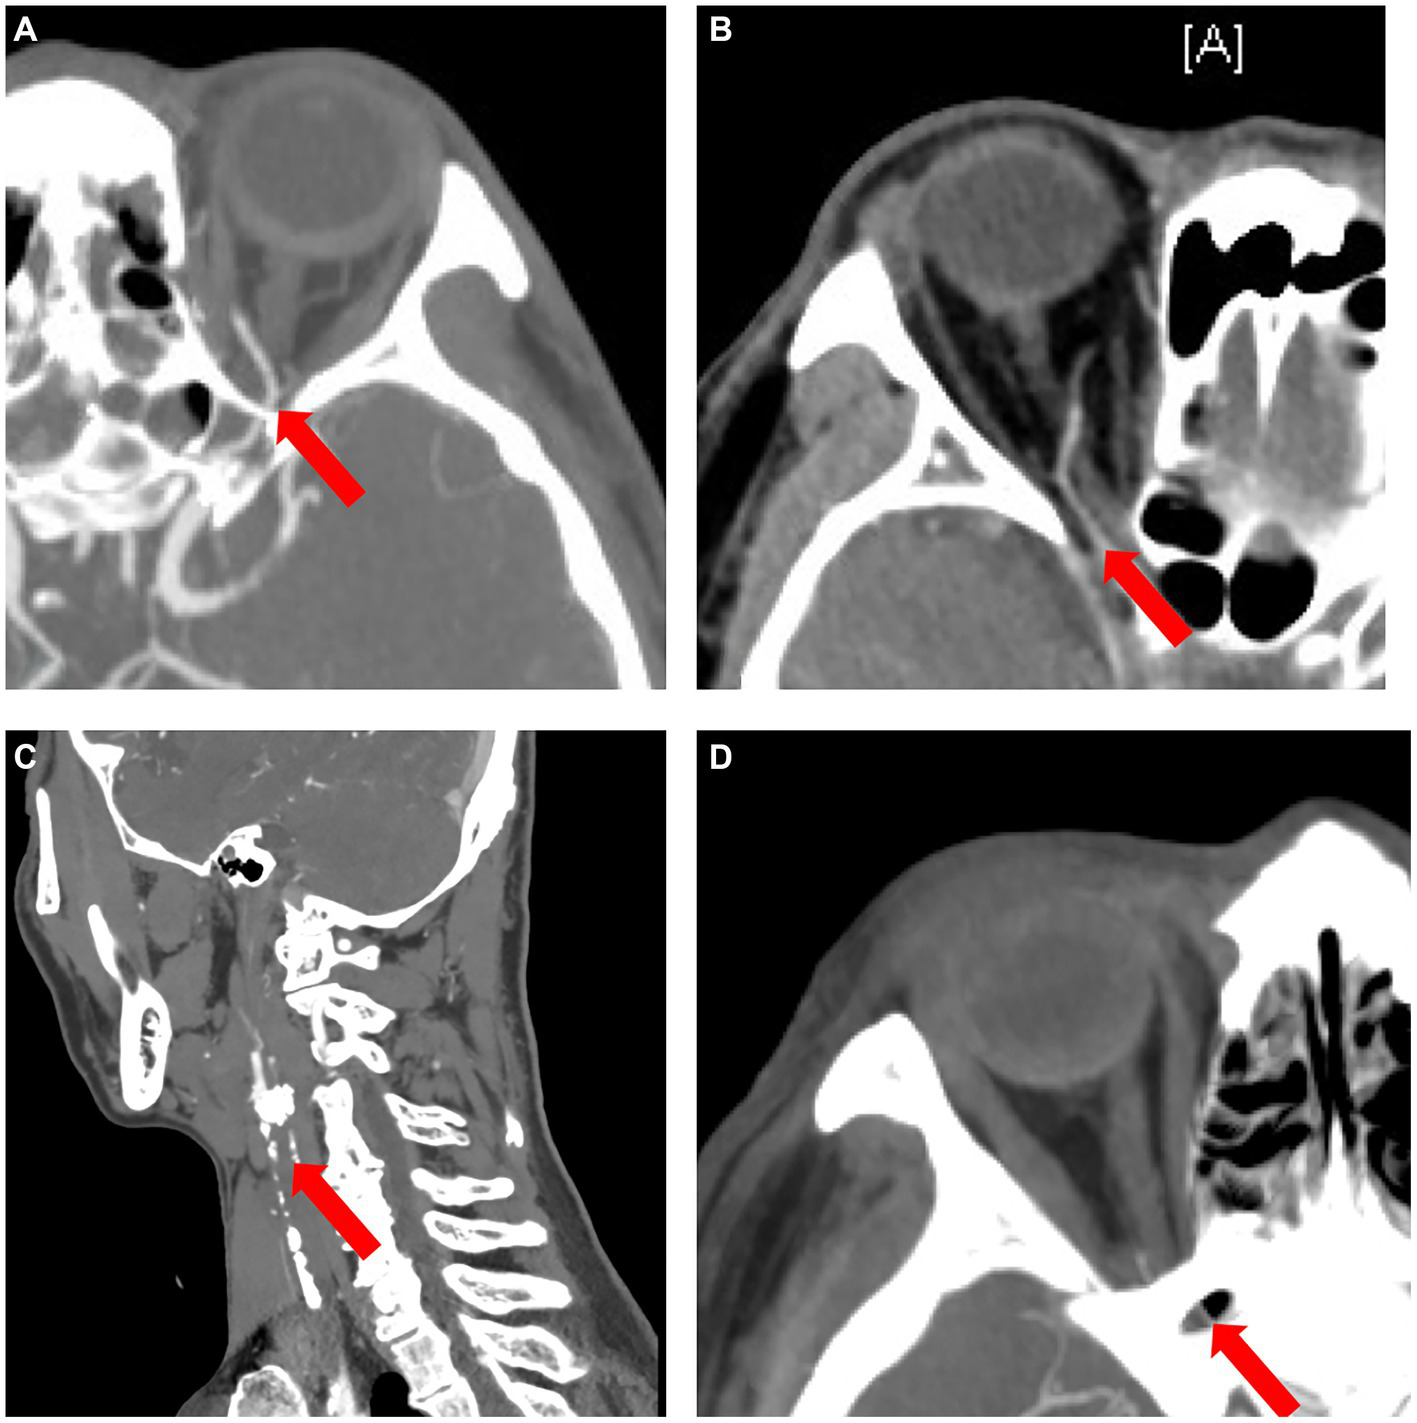

Of the 5 types, type 4 OVA presenting with reversed blood flow of OA on DSA (6 cases) was the most dangerous, with the probability of OIS, NVG and stroke being 100% (6 cases), 100% (6 cases), and 50% (3 cases), respectively. Of the 27 enrolled cases, OIS, NVG, ipsilateral ICAO, and severe (≥ 70%) stenosis of the ipsilateral ICA on CTA were individual clinical features that were potentially minimally invasive predictors for type 4 OVA. AUCs for predicting type 4 OVA were 0.95, 0.93, and 1.00, respectively. The sensitivity, specificity, and AUC for the seven scenarios (A, B, C, D, E, F, and G) are listed in Table 4. The ophthalmic artery features on CTA are depicted in Figure 8.

Figure 8

The ophthalmic artery features on CTA. (A) Normal control case presenting with good visualization of the trunk OA (red arrow) of the OA. (B) Type 4 OVA presenting with reversed visualization of blood flow in the trunk OA (red arrow) on DSA from Case No. 6, also showing a narrowed and stiff OA similar to the type 5 OVA on CTA. (C) Another type 4 OVA showing complete ICAO (red arrow) on CTA in Case No. 11. (D) Type 3 OVA presenting with no visualization of the distal trunk OA (red arrow) on DSA, also showing no visualization of the OA on CTA in Case No. 14. CTA, computed tomographic angiography; DSA, digital subtraction angiography; ICAO, internal carotid artery occlusion; OA, ophthalmic artery; OVA, ocular vascular accident.

The best individual CTA feature for predicting type 4 OVA was scenario D [ipsilateral ICAO or severe (≥ 70%) stenosis of the ipsilateral ICA ≥70%]. The sensitivity, specificity, and AUC were 100, 100%, and 1.00, respectively (p < 0.001). When ≥30% stenosis of the ipsilateral ICA occurred, the best combination of features was F and G. That is, their predictive performance was the same when ≥30% stenosis of the ipsilateral ICA was combined with OIS or NVG, with a sensitivity, specificity, and AUC of 100, 90%, and 0.95, respectively (p = 0.001).